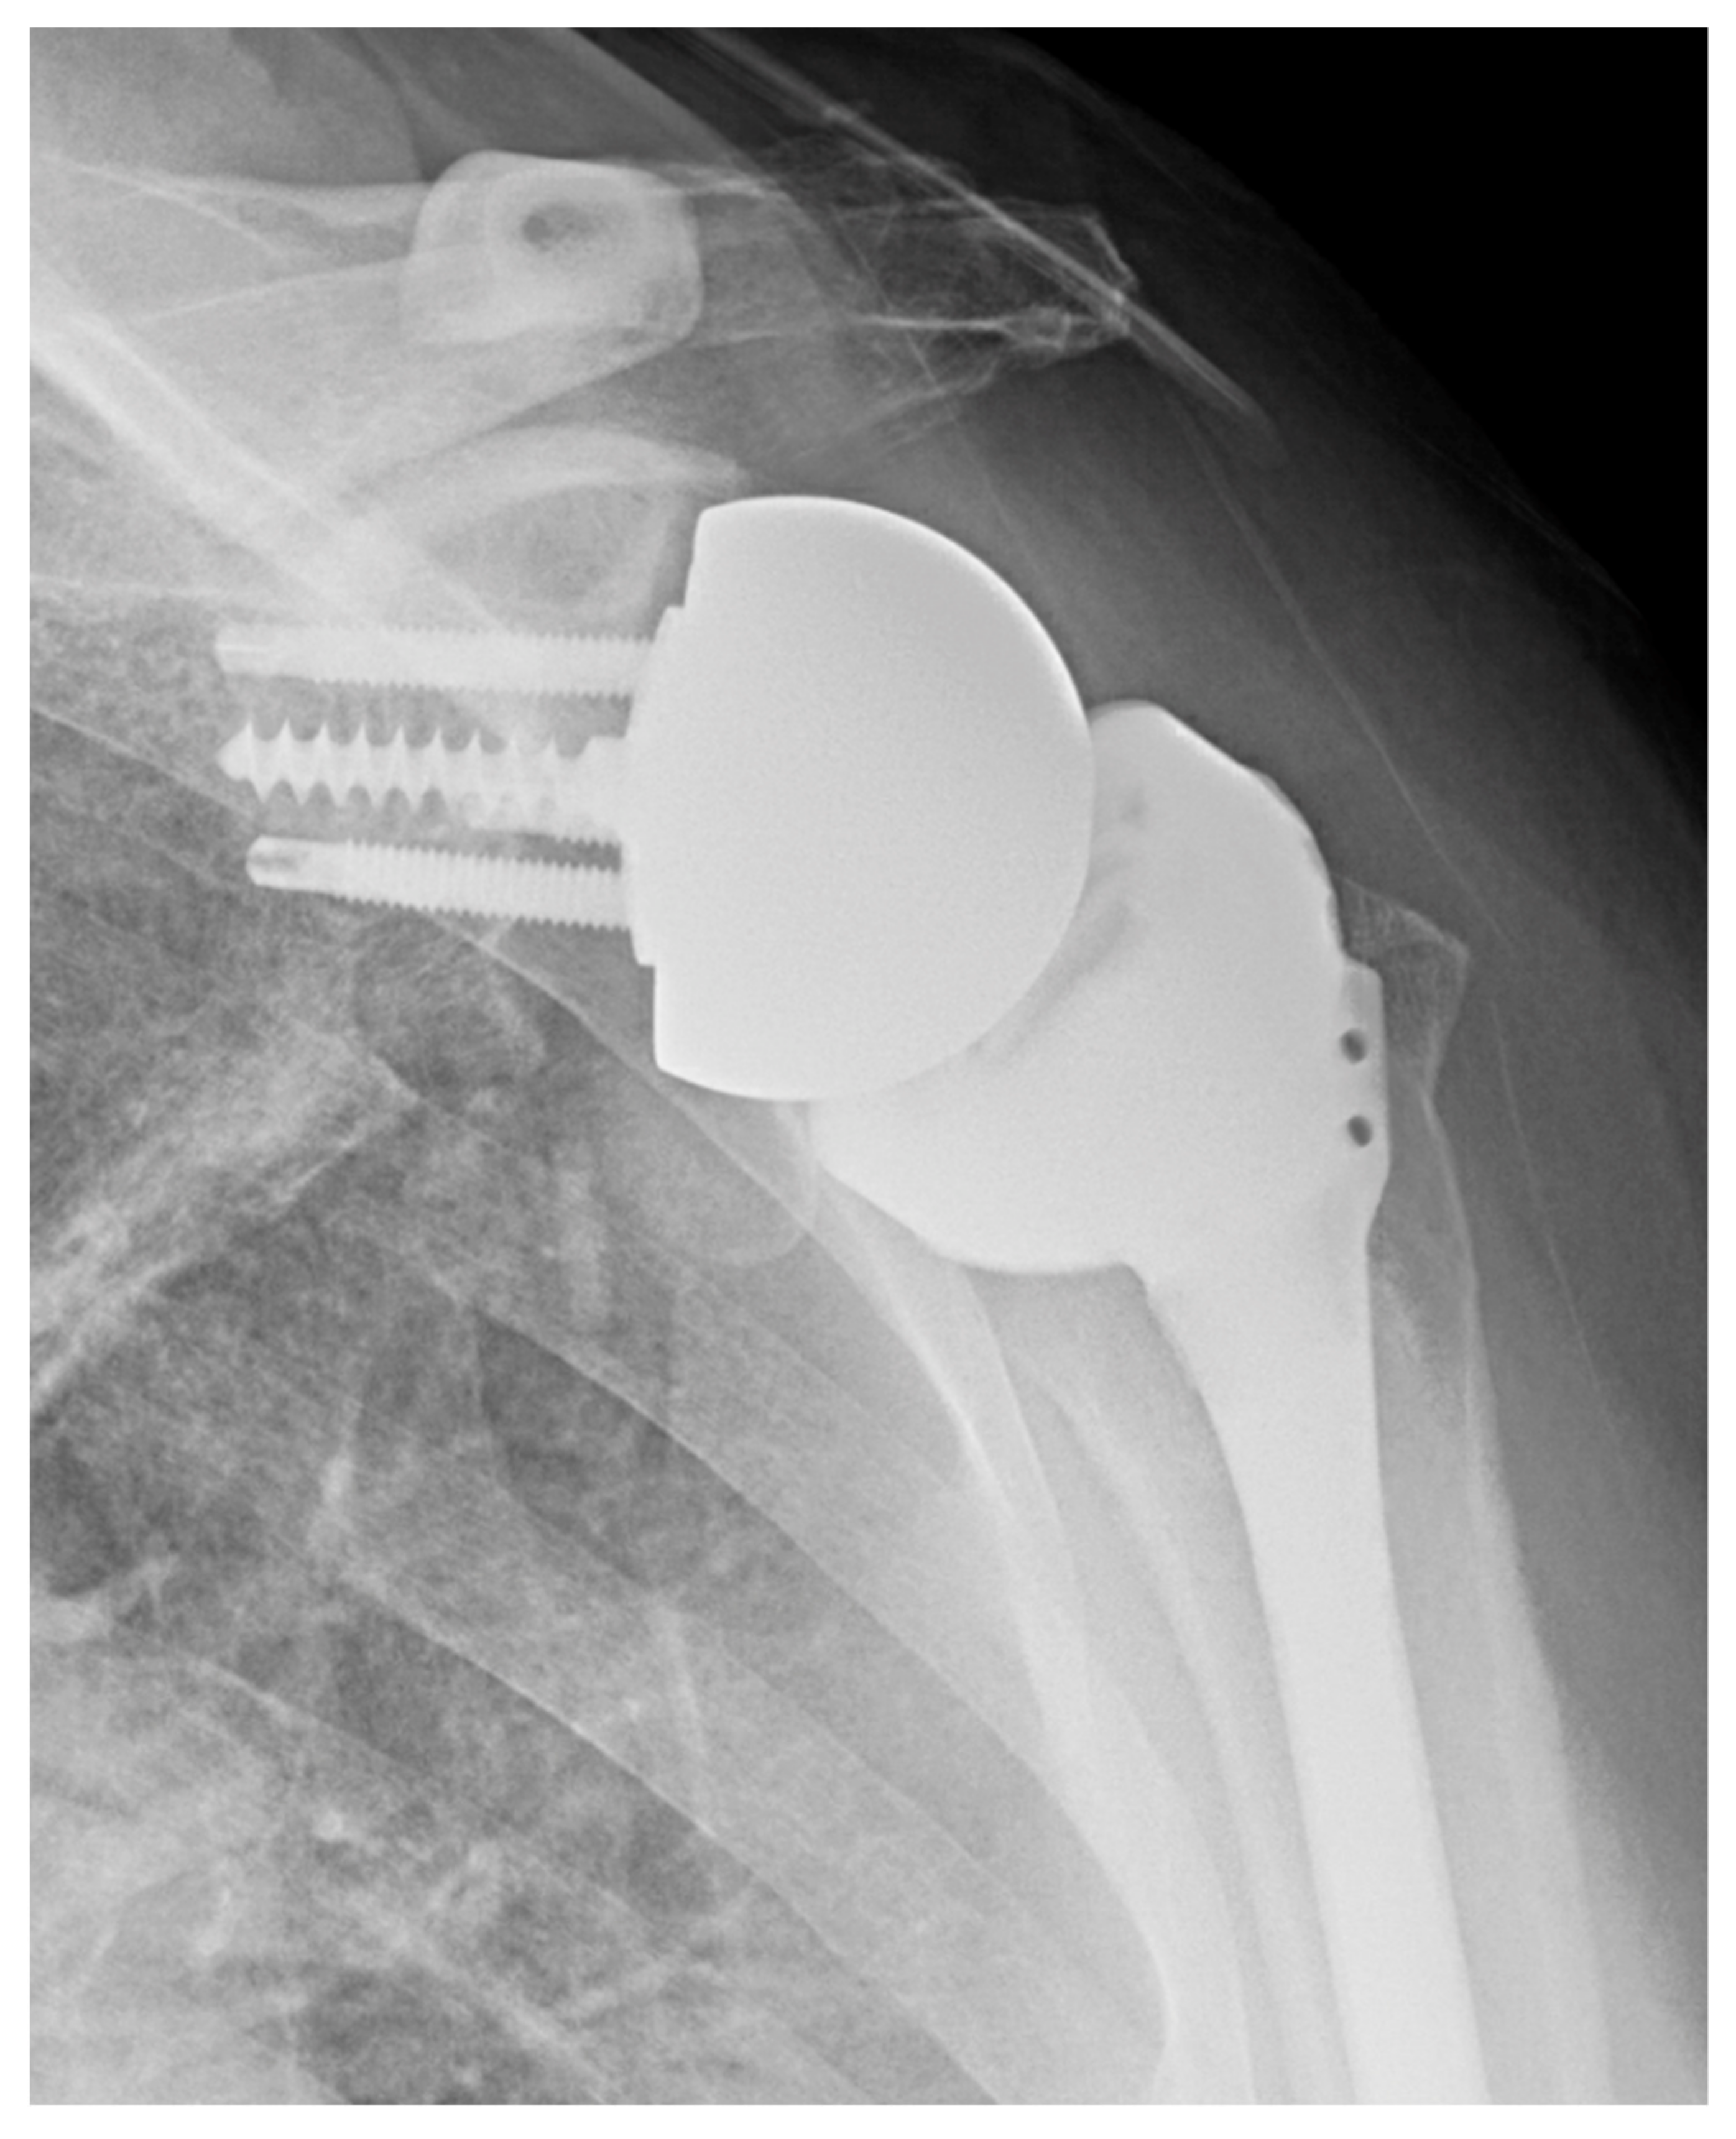

3.1. Combined Humeral and Glenoid Component Innovations

Lateralization

4.1. Convertible Implants